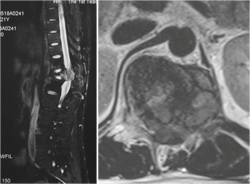

下面这个病人是个25岁的青年男性,因为下肢无力在当地医院就诊,发现T12肿瘤压迫脊髓。为了挽救神经功能,当地医生给病人做了后路椎板切除减压,椎体内肿瘤刮除及椎弓根螺钉固定手术。术后肿瘤的病理结果回报为骨巨细胞瘤。虽然神经功能改善明显,步行出院,但1年半之后肿瘤复发,不仅再次压迫脊髓而且肿瘤蔓延到相邻的3节脊椎。

图1-1,男性,25岁,术前MRI显示T12椎体、附件及椎旁肿瘤,累及椎管压迫脊髓。

图1-4,术后1年半MRI显示肿瘤复发,而且再次侵及椎管造成脊髓压迫。